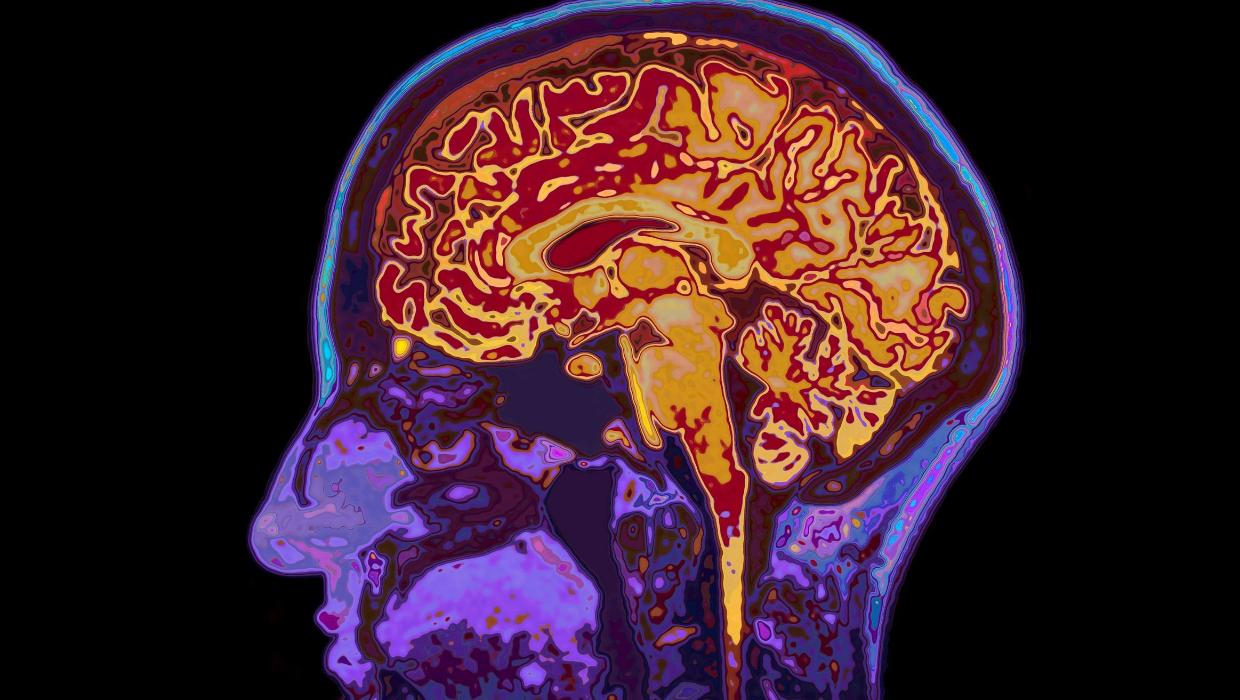

New Study Reveals Brain Development Stages Up to Age 32

Recent research conducted by the University of Cambridge has unveiled significant insights into the timeline of human brain development. The study identifies five key epochs in brain maturation, suggesting that the brain remains in a state of adolescence until approximately 32 years of age. Additionally, the research indicates that signs of ageing begin to manifest around 66 years.

According to the research, the first epoch occurs during early childhood, where foundational cognitive skills begin to form. The second epoch, spanning from childhood to early adolescence, sees significant advancements in social and emotional processing. This stage is crucial for developing interpersonal skills and emotional intelligence.

The third epoch, which extends from adolescence to early adulthood, is marked by the maturation of decision-making abilities and risk assessment. This period is essential as it shapes a person’s ability to navigate complex social environments and make informed choices.

Finally, the transition into adulthood and beyond represents the fourth epoch, where the brain continues to adapt and refine its functions. The study emphasizes that the brain’s flexibility during these years contributes significantly to lifelong learning and adaptability.

The research also stresses the importance of understanding when ageing begins to affect cognitive functions. Around 66 years of age, changes in brain structure and function may lead to noticeable declines in memory and processing speed. Recognizing these changes can help individuals and healthcare providers develop strategies to mitigate cognitive decline.